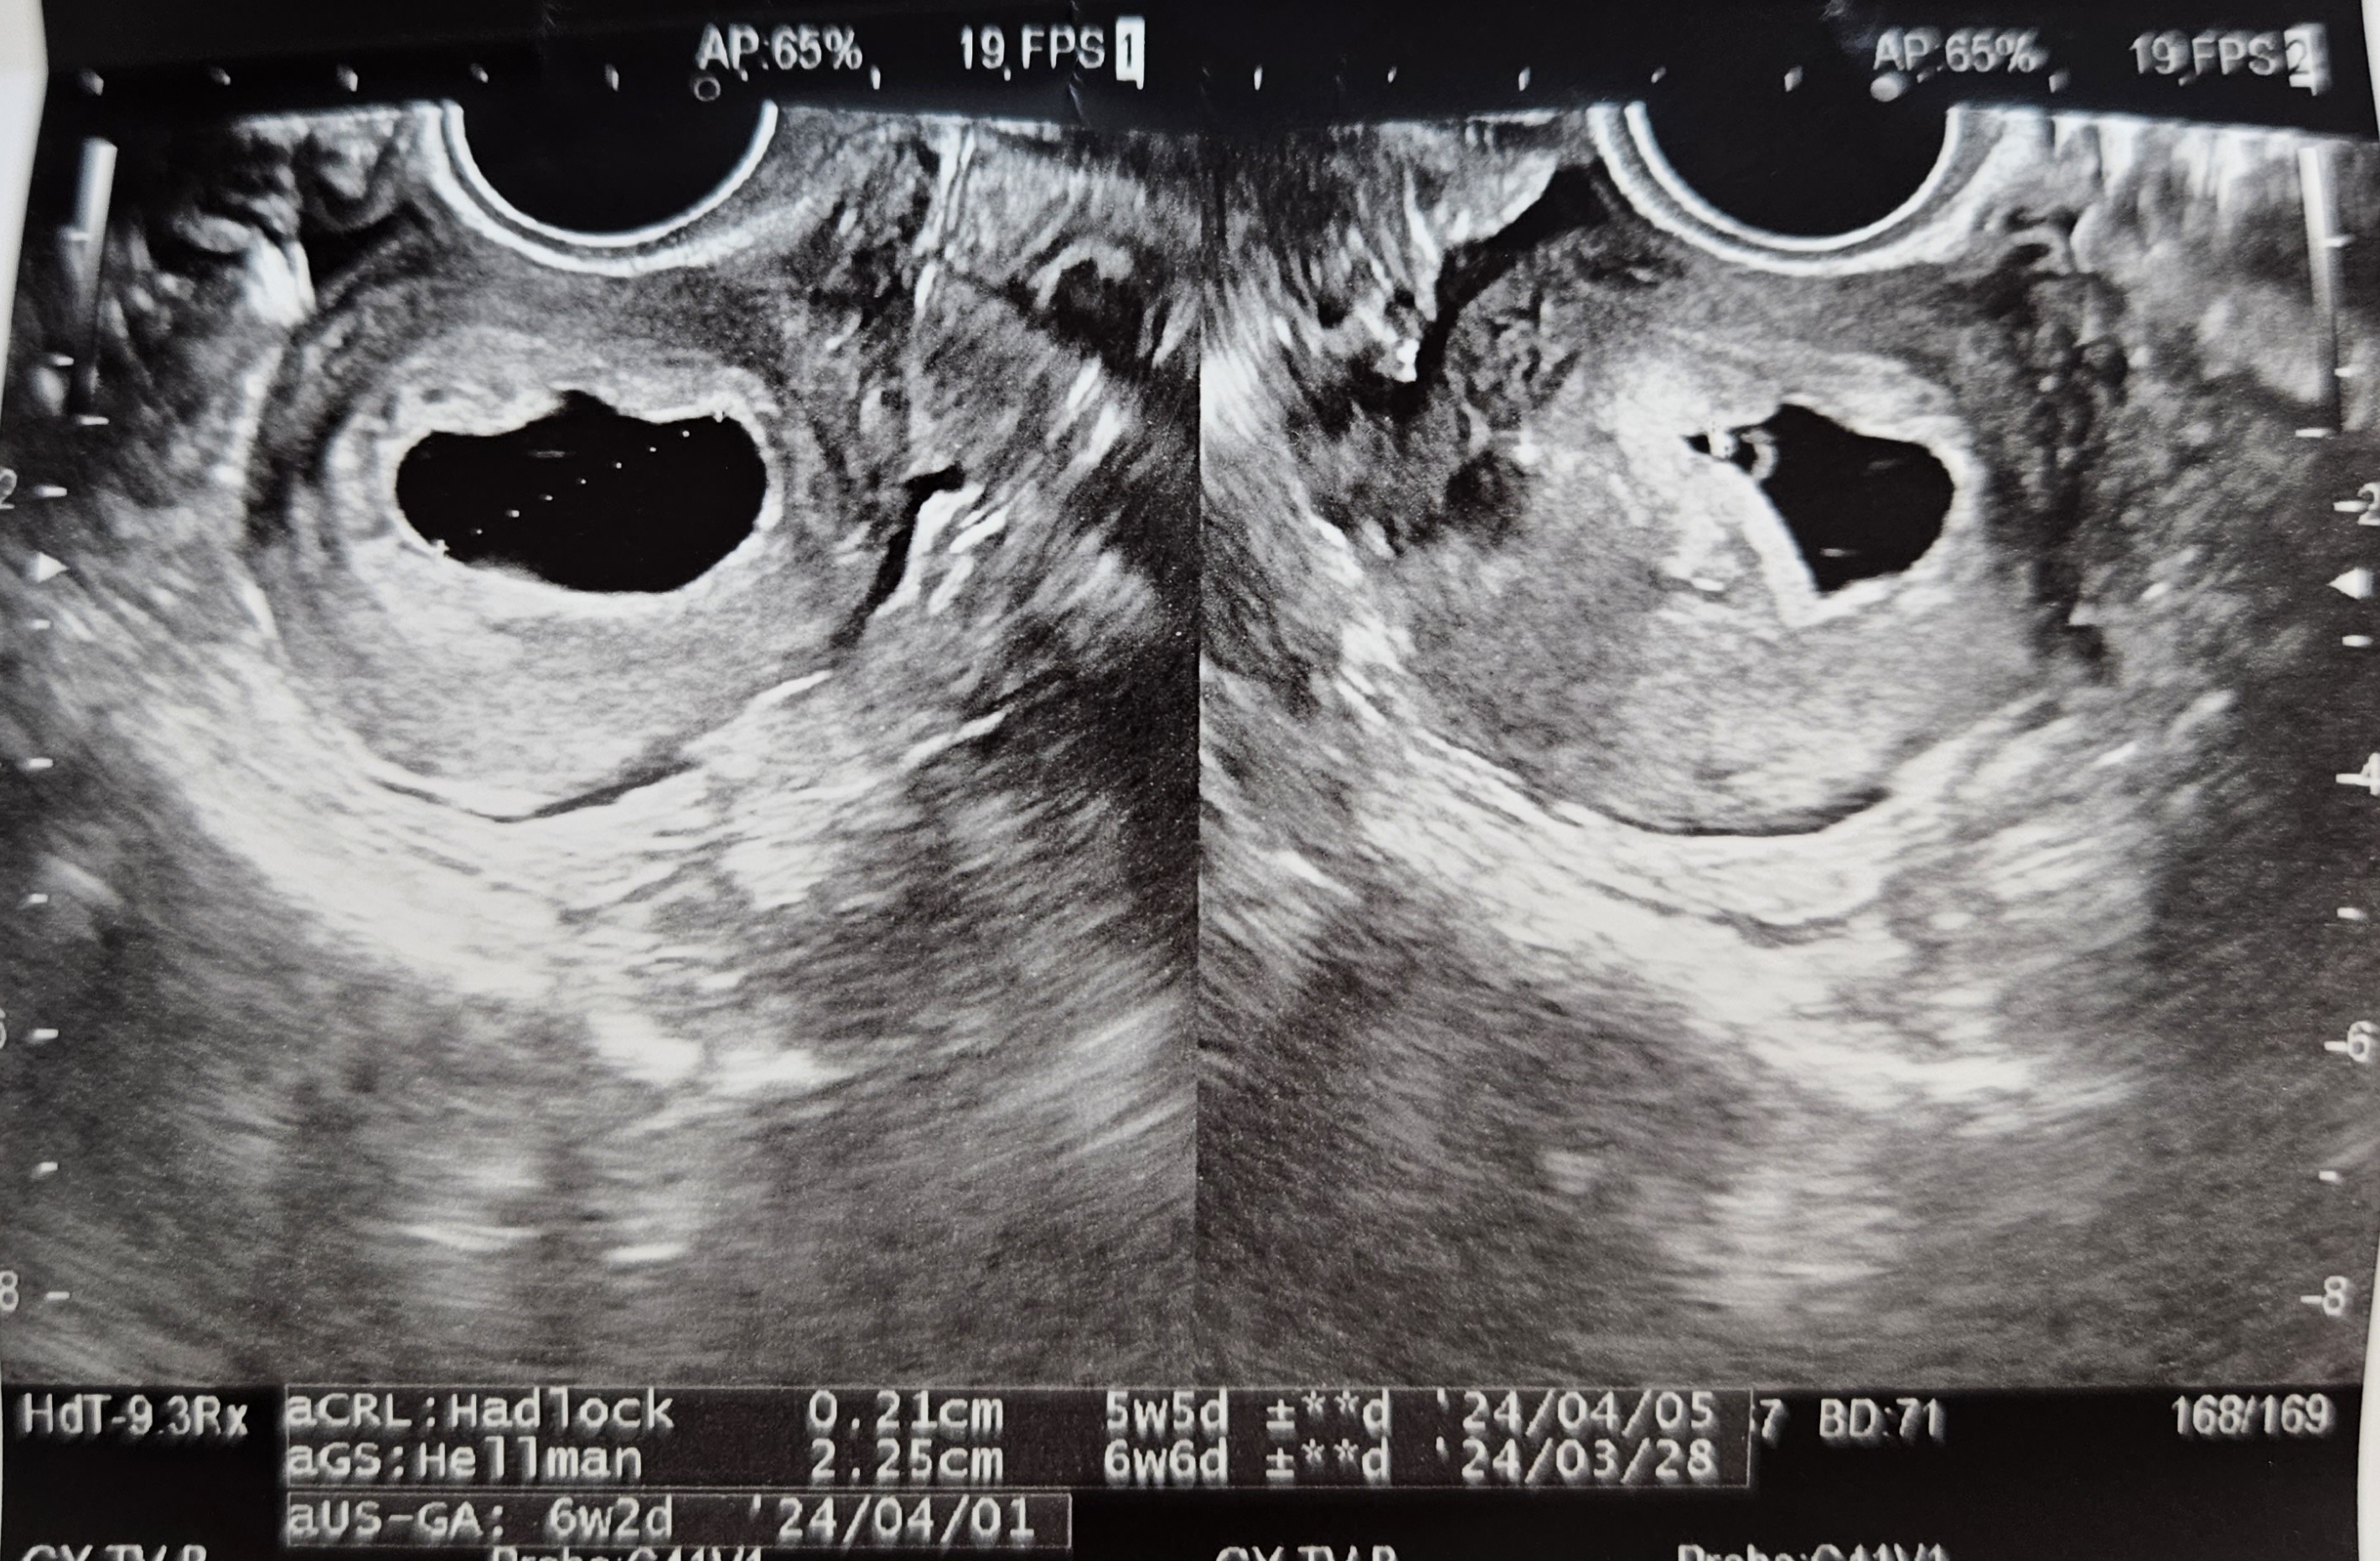

서울역차 ) 6주-7주차 초음파 심장깜빡임/심장소리/주수보다 작은 아기/갈색혈 지속 본문

초음파를 보자마자 난황 옆에 아기가 있는 걸 볼 수 있었어요!!

정말 예쁜 다이아몬드 반지죠 ㅠ_ㅠ

그런데 아직 아기 크기가 작아서 심장소리를 못듣고 심장 깜빡임만 확인하고 왔어요.

(서울역차병원은 아기크기가 0.5cm 미만이면, 아기에게 좋지 않다고 심장소리를 안들려주세요..)

저 조그마한 데에서 심장이 반짝반짝 뛰고 있는데 너무 신기한거 있죠..

그런데 오늘이 이식 기준으로 6주 4일차인데, 아기 크기는 아직 5주 5일 크기밖에 안되더라구요..

걱정되는 마음으로 진료실에 가서 교수님 뵈었는데, 교수님도 조금 더 지켜보자고 하셨어요.

7주차 진료보러 갔을 때에는 아기가 통통 해지고 조금 컸더라구요.

보통 이 때에는 아기가 1mm씩 자란다는데, 딱 자랄만큼 자라줬네욤 ㅋㅋ

초음파쌤이 아기 잘 컸다고 너무 걱정하지 말라고 좋은 말씀 해주셨구요~

이 날 심장소리도 들었는데 113bpm으로 쿵쿵쿵쿵 잘 뛰어주고 있었어요.

아직도 주수 대비 작은 아기라 걱정이 되긴 했으나, 교수님께서 이 시기에 제가 할 수 있는 건 없다고 하시더라구요..

그리고 심장 소리도, bpm도 아주 좋으니 문제 없을꺼라고 좋은말씀 해주셨어요 ㅎㅎ

초음파상 피고임이 보이긴 하지만 크기가 크진 않고, 초기에 갈색혈이 보이는건 자주 있는 현상이라고 하시더라구요..